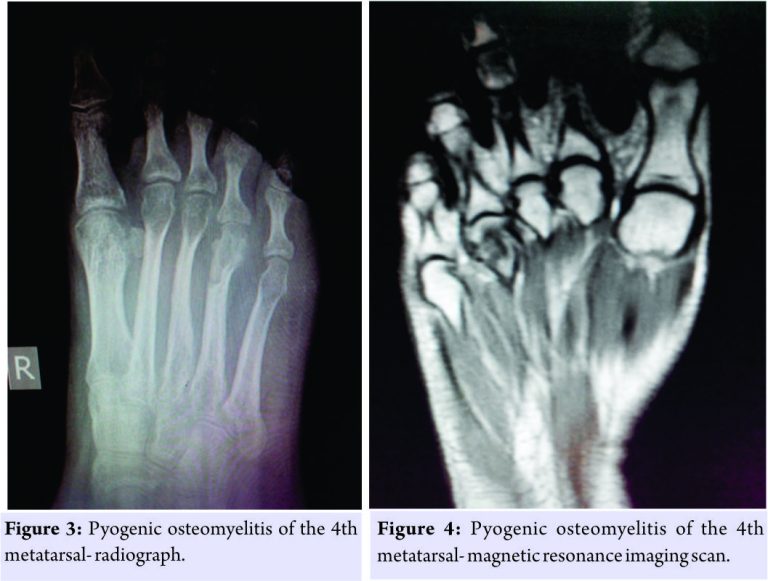

Case 2

A 20-year-old young woman came with complaints of pain in the right foot for 3 months. She also complained of on and off fever. There was neither any history of trauma nor of Koch’s contact. On examination, there was a mild swelling over the dorsum of right foot just around the fourth metatarsal. The laboratory values showed- hemoglobin of 12.1 g%, total count of 6710 cells/mm3, differential counts of N30/L66/E1/M3/B0, ESR of 54 mm/hr, and C-reactive protein of 1.2 mg/dl. The radiograph showed a lytic lesion in the head of the fourth metatarsal (Fig. 3) which was also confirmed on magnetic resonance imaging (MRI) (Fig. 4). Curettage of the lesion was done and tissue sample was taken for histopathological examination. The biopsy report was suggestive of chronic osteomyelitis. A sample was sent for pus culture which showed no growth. Broad spectrum antibiotics were given for 6 weeks. At 18-month follow-up, the patient was asymptomatic.